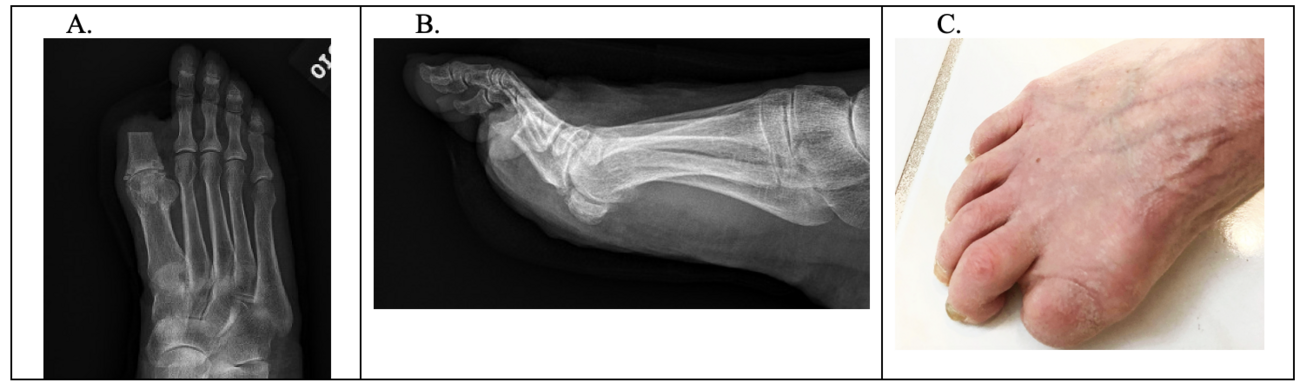

A 66-year-old female presented to the office with what appeared to be a pyogenic granuloma to the dorsal distal aspect of the right hallux (see first photo). Upon the initial exam, the patient relayed a history of developing a small reddish lesion on her nail bed. This appeared as a pyogenic granuloma and we excised it.

Two months later she presented with a similar presentation. This time, we biopsied the lesion and sent it to pathology, which diagnosed amelanotic melanoma. Before performing any radical amputation, we would first attempt a wide excision of the lesion (see second photo). The patient then went to the operating room for an excisional biopsy (see third photo). The area was covered with a biologic dressing while awaiting pathology results (see fourth photo).

Pathology came back as a PT2Nx. The lesion showed that the medial margin demonstrated in situ melanoma remaining and that there were minimal clean margins on the plantar aspect of the prior specimen, defined as a Clark level 4 (see fifth photo). Oncology recommended that the patient have a distal Syme amputation and sentinel node biopsy (see sixth photo).

The patient underwent a partial hallux amputation with primary skin closure by the authors (see seventh photo). Additionally, general surgery performed sentinel lymph node biopsy.